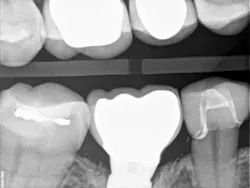

Recently, I changed my protocol for doing Class II dental restorations. I have started using indirect restorations more often. Depending on the size of the restoration, I now use indirect composites, inlays, onlays, and occasionally full-coverage crowns. Using indirect restorations allows one to control the emergence profile of the restoration and also ensures tight proximal and broad interproximal contacts. See Figures 3 through 6.

present at DL line angle not seen on radiograph.

food debris in the contact area.

embrasure space. Distal of No. 28 was restored as well;

not seen in this radiograph.